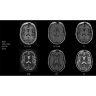

Система SIGNA Pioneer воплощает поразительные достижения в области визуализации. Передовая технология Total Digital Imaging (TDI) позволяет добиться большей четкости изображений и на четверть повысить соотношение сигнал/шум.

• Технология Direct Digital Interface (DDI) использует независимый аналого-цифровой преобразователь для оцифровки сигнала от каждого из 97 радиочастотных каналов, что обеспечивает значительное увеличение качества за счет уменьшения фонового шума.

• Технология Digital Surround Technology (DST) — это новая технология объемной оцифровки данных, объединяющая сигналы от каждого элемента катушки. Прекрасное соотношение сигнал/шум и чувствительность поверхностных катушек в сочетании с превосходной однородностью и высокой проникающей способностью встроенной радиочастотной катушки — все это позволяет создавать качественные изображения не только позвоночника, но и всего тела.